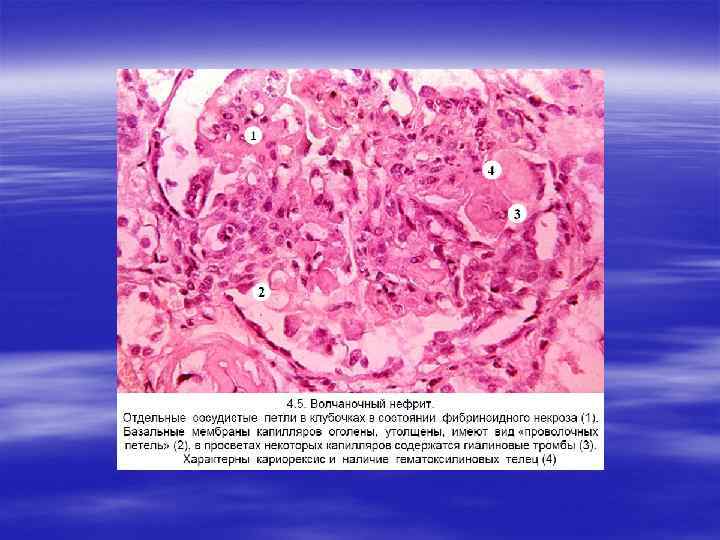

§ II. Вторичные гломерулонефриты, которые развиваются при системных заболеваниях, чаще иммунной природы, к которым относятся: 1. системная красная волчанка, 2. диабет, 3. амилоидоз, 4. синдром Гудпасчера, 5. узелковый периартериит, 6. гранулематоз Вегенера.

§ Причины нефротического синдрома разнообразны: § системная красная волчанка (люпус нефрит), § диабет, § амилоидоз, § липоидный нефроз (болезнь минимальных изменений), § мембранозный гломерулонефрит,

§ Острый нефритический синдром может возникать при си стемных заболеваниях (например, при системной красной волчан ке) или развиваться вследствие первичного поражения клубочков (в частности, при остром диффузном пролиферативном гломерулонефрите).

ДИФФУЗНЫЙ ПРОЛИФЕРАТИВНЫЙ ГЛОМЕРУЛОНЕФРИТ Этот вид гломерулонефрита, называемый также § Этот вид гломерулонефрита, называемый также острым гломерулонефритом, представляет собой диффузный воспалитель ный процесс иммунной природы, вызываемый антигенами эндо генного и экзогенного происхождения. § Этиология и патогенез. § Эндогенные антигены формируются при системной красной волчанке. К экзогенным антигенам относятся: § бета гемолитический стрептококк группы А типа 1, 4; § стафилококк, § вирусы инфекционного мононуклеоза, § ветряной оспы, § гепатита В, кори, паротита, вирус Коксаки.